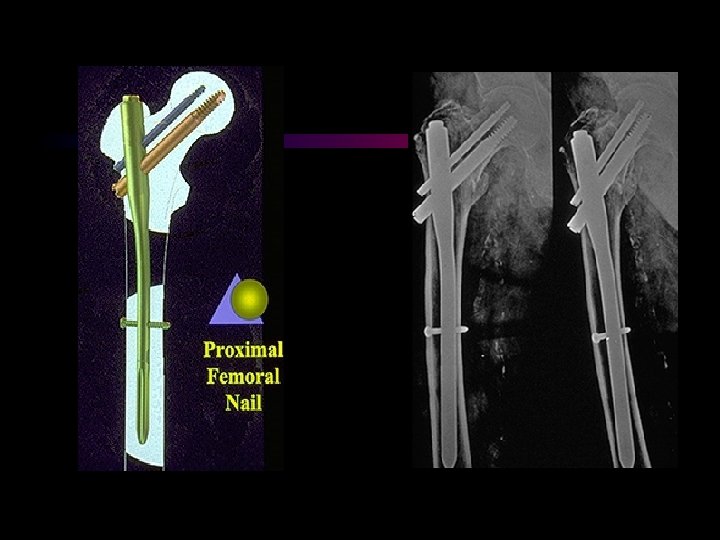

Stress measurements at the end of the nail. A comparative study between the -nail and the PFN. E. Euler. LMU München 1999 A photoelastic loading study Stress by cyclic loading with 700 N up to 7 times as high in the Gamma nail as in the PFN DHS + TSP

Stress measurements at the end of the nail. A comparative study between the -nail and the PFN. E. Euler. LMU München 1999 A photoelastic loading study Stress by cyclic loading with 700 N up to 7 times as high in the Gamma nail as in the PFN DHS + TSP